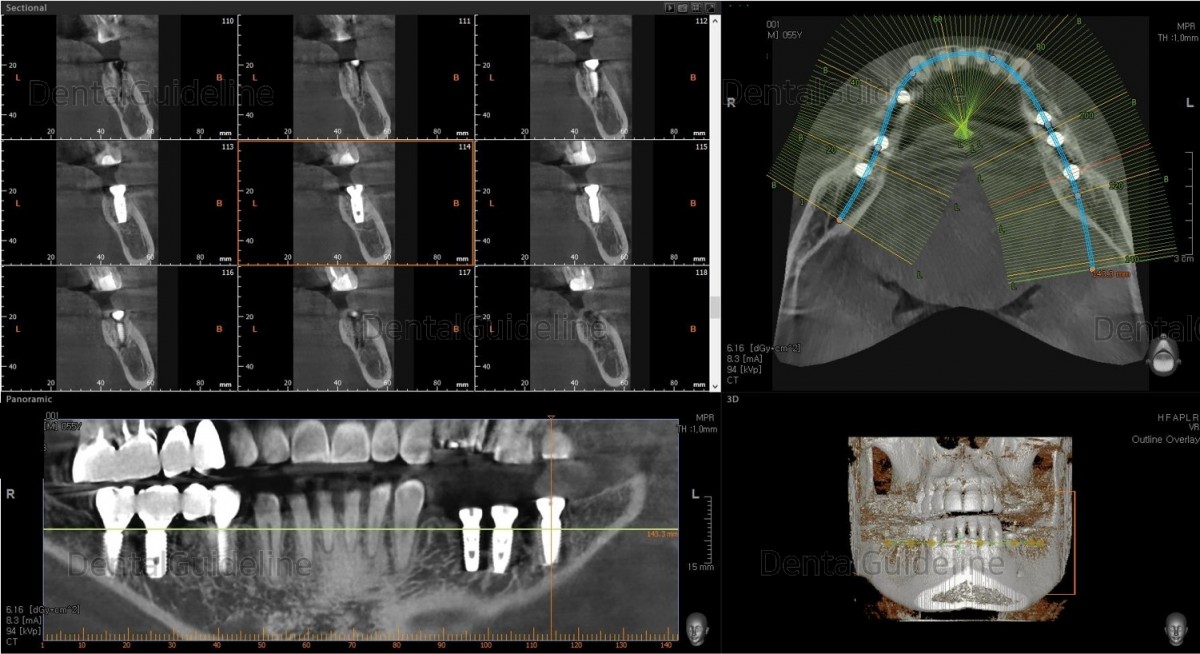

Surgery simulation to find the optimal

size, position, and direction of implants.